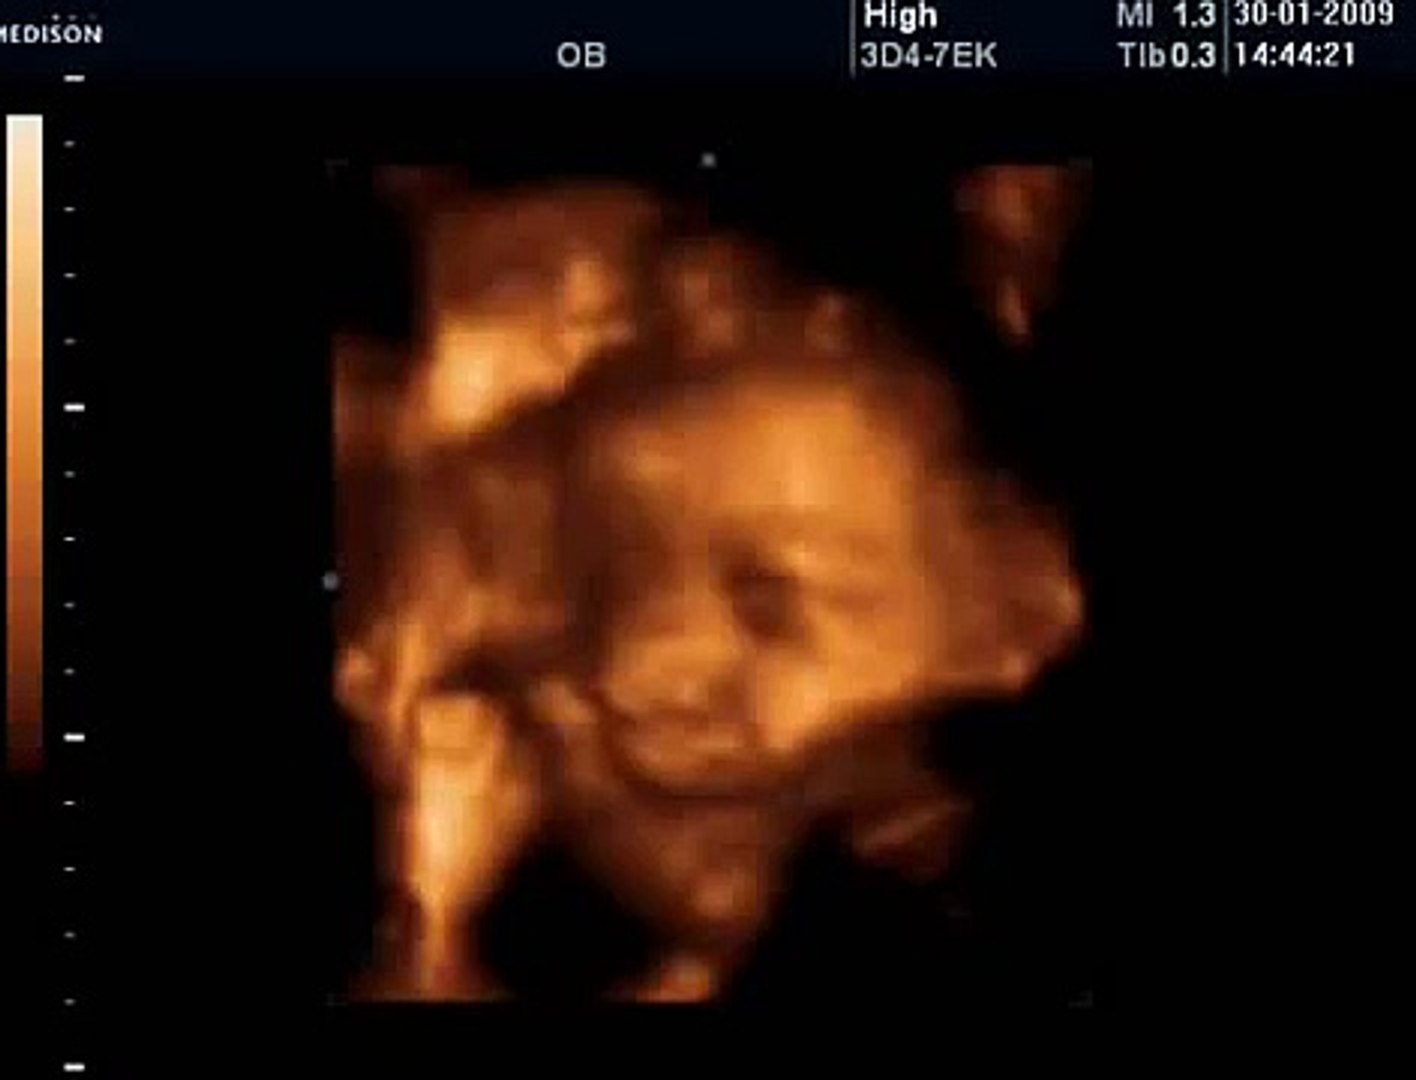

4d Dort Boyutlu Renkli Ayrintili Gebelik Ultrasonu